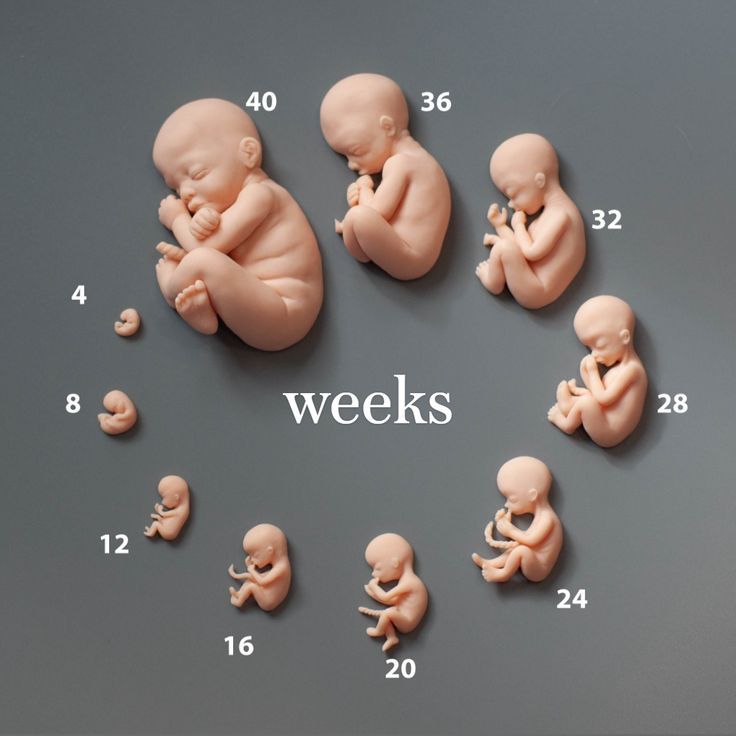

مراحل نمو الجنين شهر بشهر خلال الحمل: دليل شامل للأمهات

تعد مراحل نمو الجنين خلال أشهر الحمل من أكثر الظواهر المدهشة التي تعيشها المرأة، في خلال تسعة أشهر فقط، يتكوّن كائن بشري كامل داخل الرحم، إليكِ هذا الدليل المفصل الذي يوضح تطور الجنين شهرًا بشهر، لتتابعي نمو طفلكِ خطوة بخطوة، اكتشفي مراحل نمو الطفل داخل الرحم، من الأسبوع الأول حتى الولادة، وتعرفي على التغيرات المذهلة التي تحدث في جسمك وجسم الجنين خلال مراحل الحمل.

الشهر الأول (الأسبوع 1–4): البدايات الأولى

في هذه المرحلة من نمو الجنين تبدأ البويضة المخصبة بالانغراس داخل بطانة الرحم، ويتكون الكيس الأمنيوسي الذي سيحيط بالجنين ويحميه، تبدأ المشيمة في التشكل لتغذي الجنين، تظهر ملامح الوجه الأولية، وتبدأ نبضات القلب، في نهاية هذا الشهر، يكون حجم الجنين أصغر من حبة أرز.

الشهر الثاني (الأسبوع 5–9): تشكل الأعضاء الحيوية

ثم يبدأ تطور الجنين من وجه الجنين وتنمو براعم الأطراف، تبدأ أعضاء مهمة مثل الدماغ والجهاز الهضمي بالتشكل، وتبدأ العظام في التكون، ويمكن سماع نبضات القلب بالموجات فوق الصوتية في الأسبوع السادس، يوصى خلال هذه المرحلة من نمو الجنين بتناول فيتامينات الحمل، خاصة حمض الفوليك وأوميغا 3.

الشهر الثالث (الأسبوع 10–14): نمو مكتمل لأطراف الجنين

تكتمل الأطراف والأصابع، وتبدأ الأظافر والأذنان في التكوّن، وفي نهاية هذا الشهر، يكون نمو الجنين قد اكتمل نموه من حيث الأعضاء الأساسية، ويبلغ طوله 10 سم تقريبًا، كما تنخفض احتمالية الإجهاض بشكل ملحوظ.

الشهر الرابع (الأسبوع 15–19): تطور واضح في الملامح

ينمو الشعر والجفون والرموش، وتظهر الأعضاء التناسلية بوضوح في السونار، كما يبدأ نمو الجنين بالحركة مثل المص والتثاؤب،و يبلغ طوله في هذه المرحلة نحو 15 سم.

الشهر الخامس (الأسبوع 20–24): الشعور بالحركة

تشعر الأم بحركات الطفل الأولى، وتغطي طبقة الطلاء الجبني الجلد، حيث يصل طوله إلى 25 سم، في حال الولادة المبكرة بعد الأسبوع 23، يحتاج الطفل إلى رعاية مكثفة.

الشهر السادس (الأسبوع 25–30): تطور الحواس

يصبح جلد الجنين محمرًا وشفافًا، وتكتمل بصمات الأصابع، يستجيب الطفل للأصوات والضوء، قد تشعرين بفواقه، وطوله حوالي 30 سم ووزنه يصل إلى 900 غرام.

الشهر السابع (الأسبوع 26–29): زيادة الوزن والنمو

يتطور الجهاز العصبي والسمعي، يبدأ الطفل بتخزين الدهون، ويصبح أكثر نشاطًا، و طوله يصل إلى 35 سم، ووزنه بين 900 غرام و1.8 كجم.

الشهر الثامن (الأسبوع 30–34): استعداد تدريجي للولادة

ينمو دماغ الطفل بسرعة، وتكتمل معظم أعضائه، وكذلك الرئتان تقتربان من النضج، ويبلغ طوله حوالي 45 سم، ووزنه أكثر من 2 كجم.

الشهر التاسع (الأسبوع 35–40+): اللحظات الأخيرة

تنضج الرئتان بالكامل، و تقل حركة الطفل، ويبدأ في اتخاذ وضعية الولادة، وايضا طوله بين 45-50 سم، ووزنه قد يتجاوز 3.5 كجم.